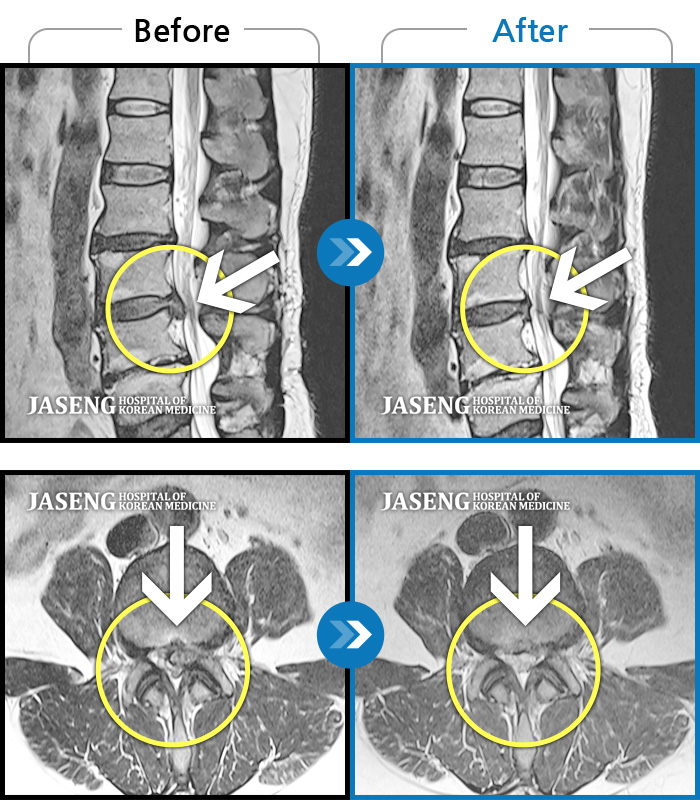

MRI 치료사례

허리디스크

광주 · 김동은 원장

허리 통증과 양측 둔부부터 허벅지, 발목 부위 저리는 증상으로 내원하셨습니다.

촬영시기

2025.05.09 ~ 2025.12.18

요추 5번과 천추 1번 사이에서 탈출된 디스크가 신경막을 압박

2017.08.26 ~ 2018.03.31